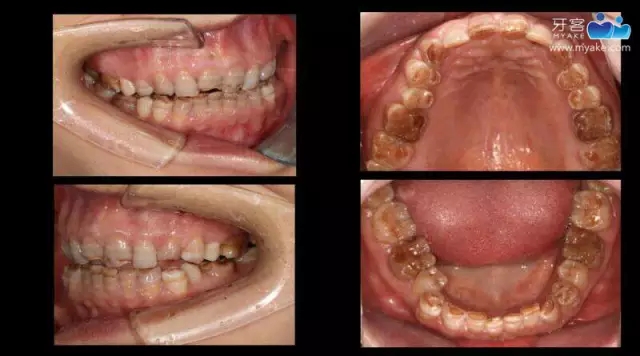

從DSD設(shè)計(jì)到瓷貼面實(shí)現(xiàn)(上)—李偉老師